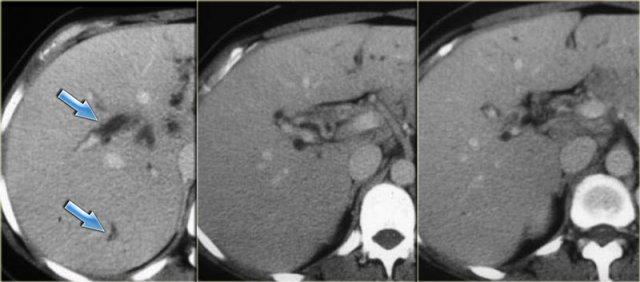

Bên trái là hình ảnh bệnh nhân với các ống mật giãn kèm sỏi trong ống (mũi tên)

Hãy quan sát hình ảnh bên trái.

Sau đó tiếp tục đọc.

Các dấu hiệu bao gồm:

- Thận xốp tủy kèm hình thành sỏi (mũi tên đỏ)

- Giãn nhẹ ống mật (mũi tên xanh dương)

- Khối giảm tỷ trọng dạng tròn ở thùy gan phải

Khối ở thùy gan phải được xác định là áp xe.

Cần lưu ý rằng áp xe gan trong giai đoạn sớm có thể có hình ảnh khá đặc.

Trong chẩn đoán phân biệt, chúng ta cũng cần xem xét khả năng u tân sinh, vì bệnh nhân mắc bệnh Caroli có nguy cơ tăng cao phát triển ung thư biểu mô đường mật.